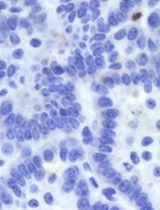

Cover of Cancer Discovery, featuring study using the protocol.

May 2014